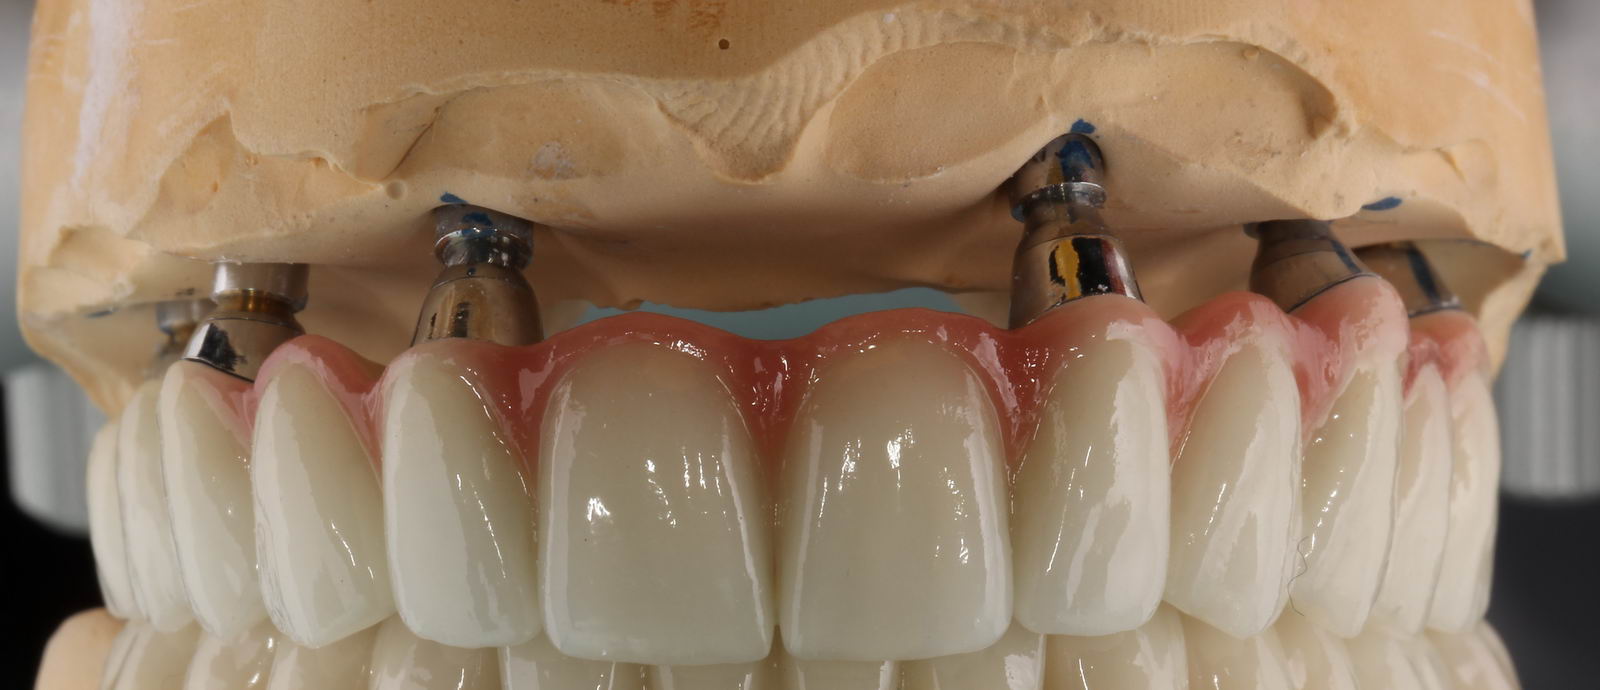

Поэтому мы разработаем для него другой, более вменяемый план лечения — несъемная конструкция с опорой на 6-8 имплантатов. Максимально естественная и функциональная. Только тогда 45-летний мужчина будет счастлив, только так мы вернём ему прежнее качество жизни. И никак иначе.

Таким же образом можно, в виде задачи «Из пункта А в пункт Б» можно рассмотреть и разрешить любую клиническую ситуацию, от простой профессиональной чистки зубов до сложного комплексного лечения, требующего участия целой команды специалистов. Важно лишь помнить, что в центре этой задачи стоите вы, пациенты, — и мы, доктора, рассматриваем ВАШУ клиническую ситуацию и выполняем ВАШИ пожелания, в меру своих возможностей и с учётом здравого смысла.